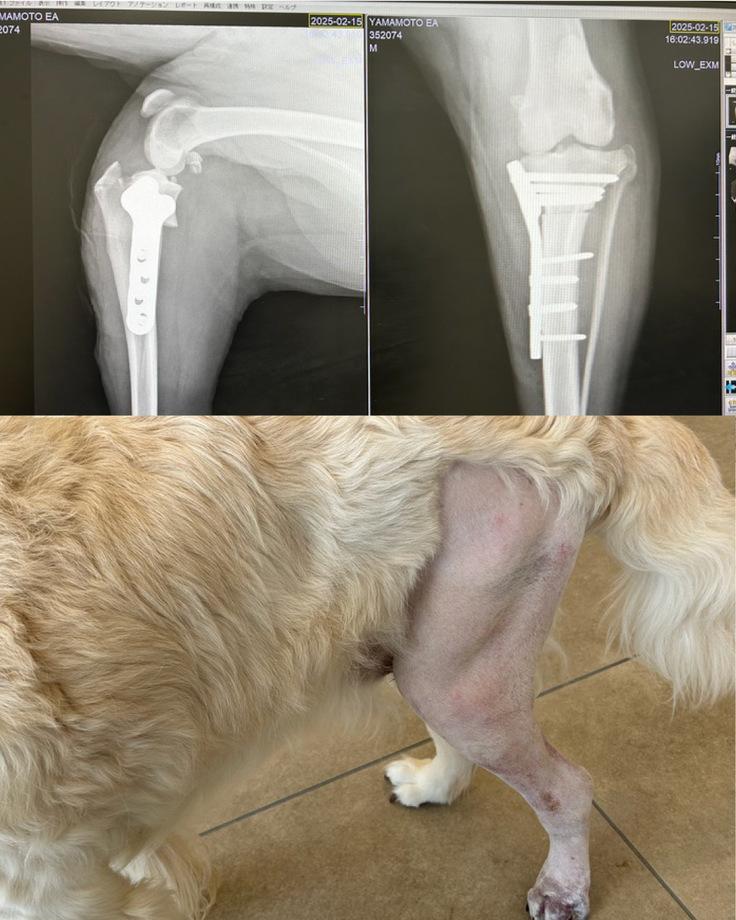

2月、術後すぐ。

術後1週間くらいなのでパンパンだし。今となっては、立ってるのが今となっては逆にすごいと思えます。足はついてるだけで体重はかかってません。

術後2週間くらい。

腫れが引いて毛が生えています。着足もできていて歩行もできます。